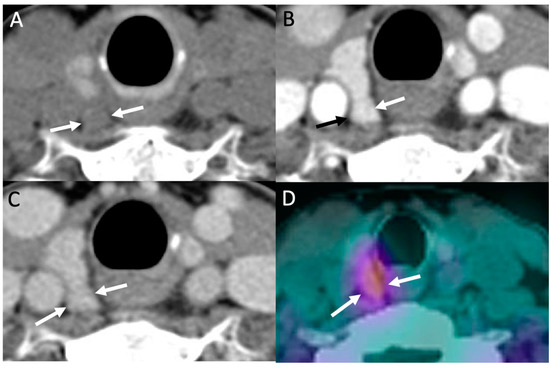

- Amadou, C.; Bera, G.; Ezziane, M.; Chami, L.; Delbot, T.; Rouxel, A.; Leban, M.; Herve, G.; Menegaux, F.; Leenhardt, L.; et al. 18F-Fluorocholine PET/CT and Parathyroid 4D Computed Tomography for Primary Hyperparathyroidism: The Challenge of Reoperative Patients. World J. Surg. 2019, 43, 1232–1242. [Google Scholar] [CrossRef] [PubMed]

- Piccardo, A.; Trimboli, P.; Rutigliani, M.; Puntoni, M.; Foppiani, L.; Bacigalupo, L.; Crescenzi, A.; Bottoni, G.; Treglia, G.; Paparo, F.; et al. Additional value of integrated 18F-choline PET/4D contrast-enhanced CT in the localization of hyperfunctioning parathyroid glands and correlation with molecular profile. Eur. J. Nucl. Med. Mol. Imaging 2018, 46, 766–775. [Google Scholar] [CrossRef]

- Pretet, V.; Rotania, M.; Helali, M.; Ignat, M.; Vix, M.; Imperiale, A. 18F-Fluorocholine PET and Multiphase CT Integrated in Dual Modality PET/4D-CT for Preoperative Evaluation of Primary Hyperparathyroidism. J. Clin. Med. 2020, 9, 2005. [Google Scholar] [CrossRef]